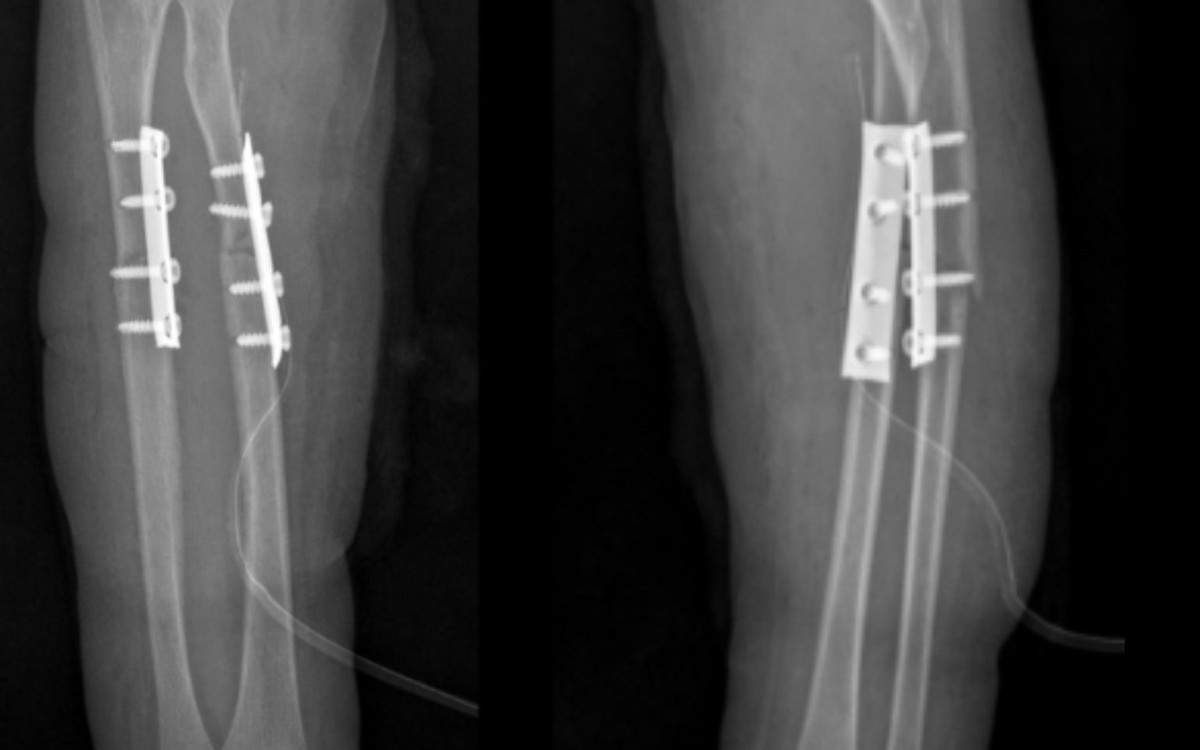

Phẫu thuật kết hợp xương cố định xương gãy, phục hồi vận động sớm - Ảnh BVCC

Sau hơn 1 giờ phẫu thuật, dưới sự hỗ trợ của hệ thống máy C-arm, ê-kíp phẫu thuật tiến hành nắn chỉnh trục xương giúp đưa hai đầu xương gãy và mảnh xương di lệch về đúng vị trí giải phẫu, khôi phục chiều dài và chức năng sấp, ngửa của cẳng tay.

Sau đó, phẫu thuật viên đặt nẹp vít cố định nhằm giữ vững hai đoạn xương, tạo điều kiện cho quá trình liền xương diễn ra đúng vị trí giải phẫu, tránh nguy cơ sai lệch hoặc biến dạng. Toàn bộ quá trình phẫu thuật được thực hiện qua một đường mổ nhỏ ở phía trước. Chỉ với một đường tiếp cận này, phẫu thuật viên có thể nắn chỉnh và cố định đồng thời cả hai xương gãy, giúp giảm tổn thương phần mềm, hạn chế mất máu và giảm đau sau mổ cho bệnh nhi.